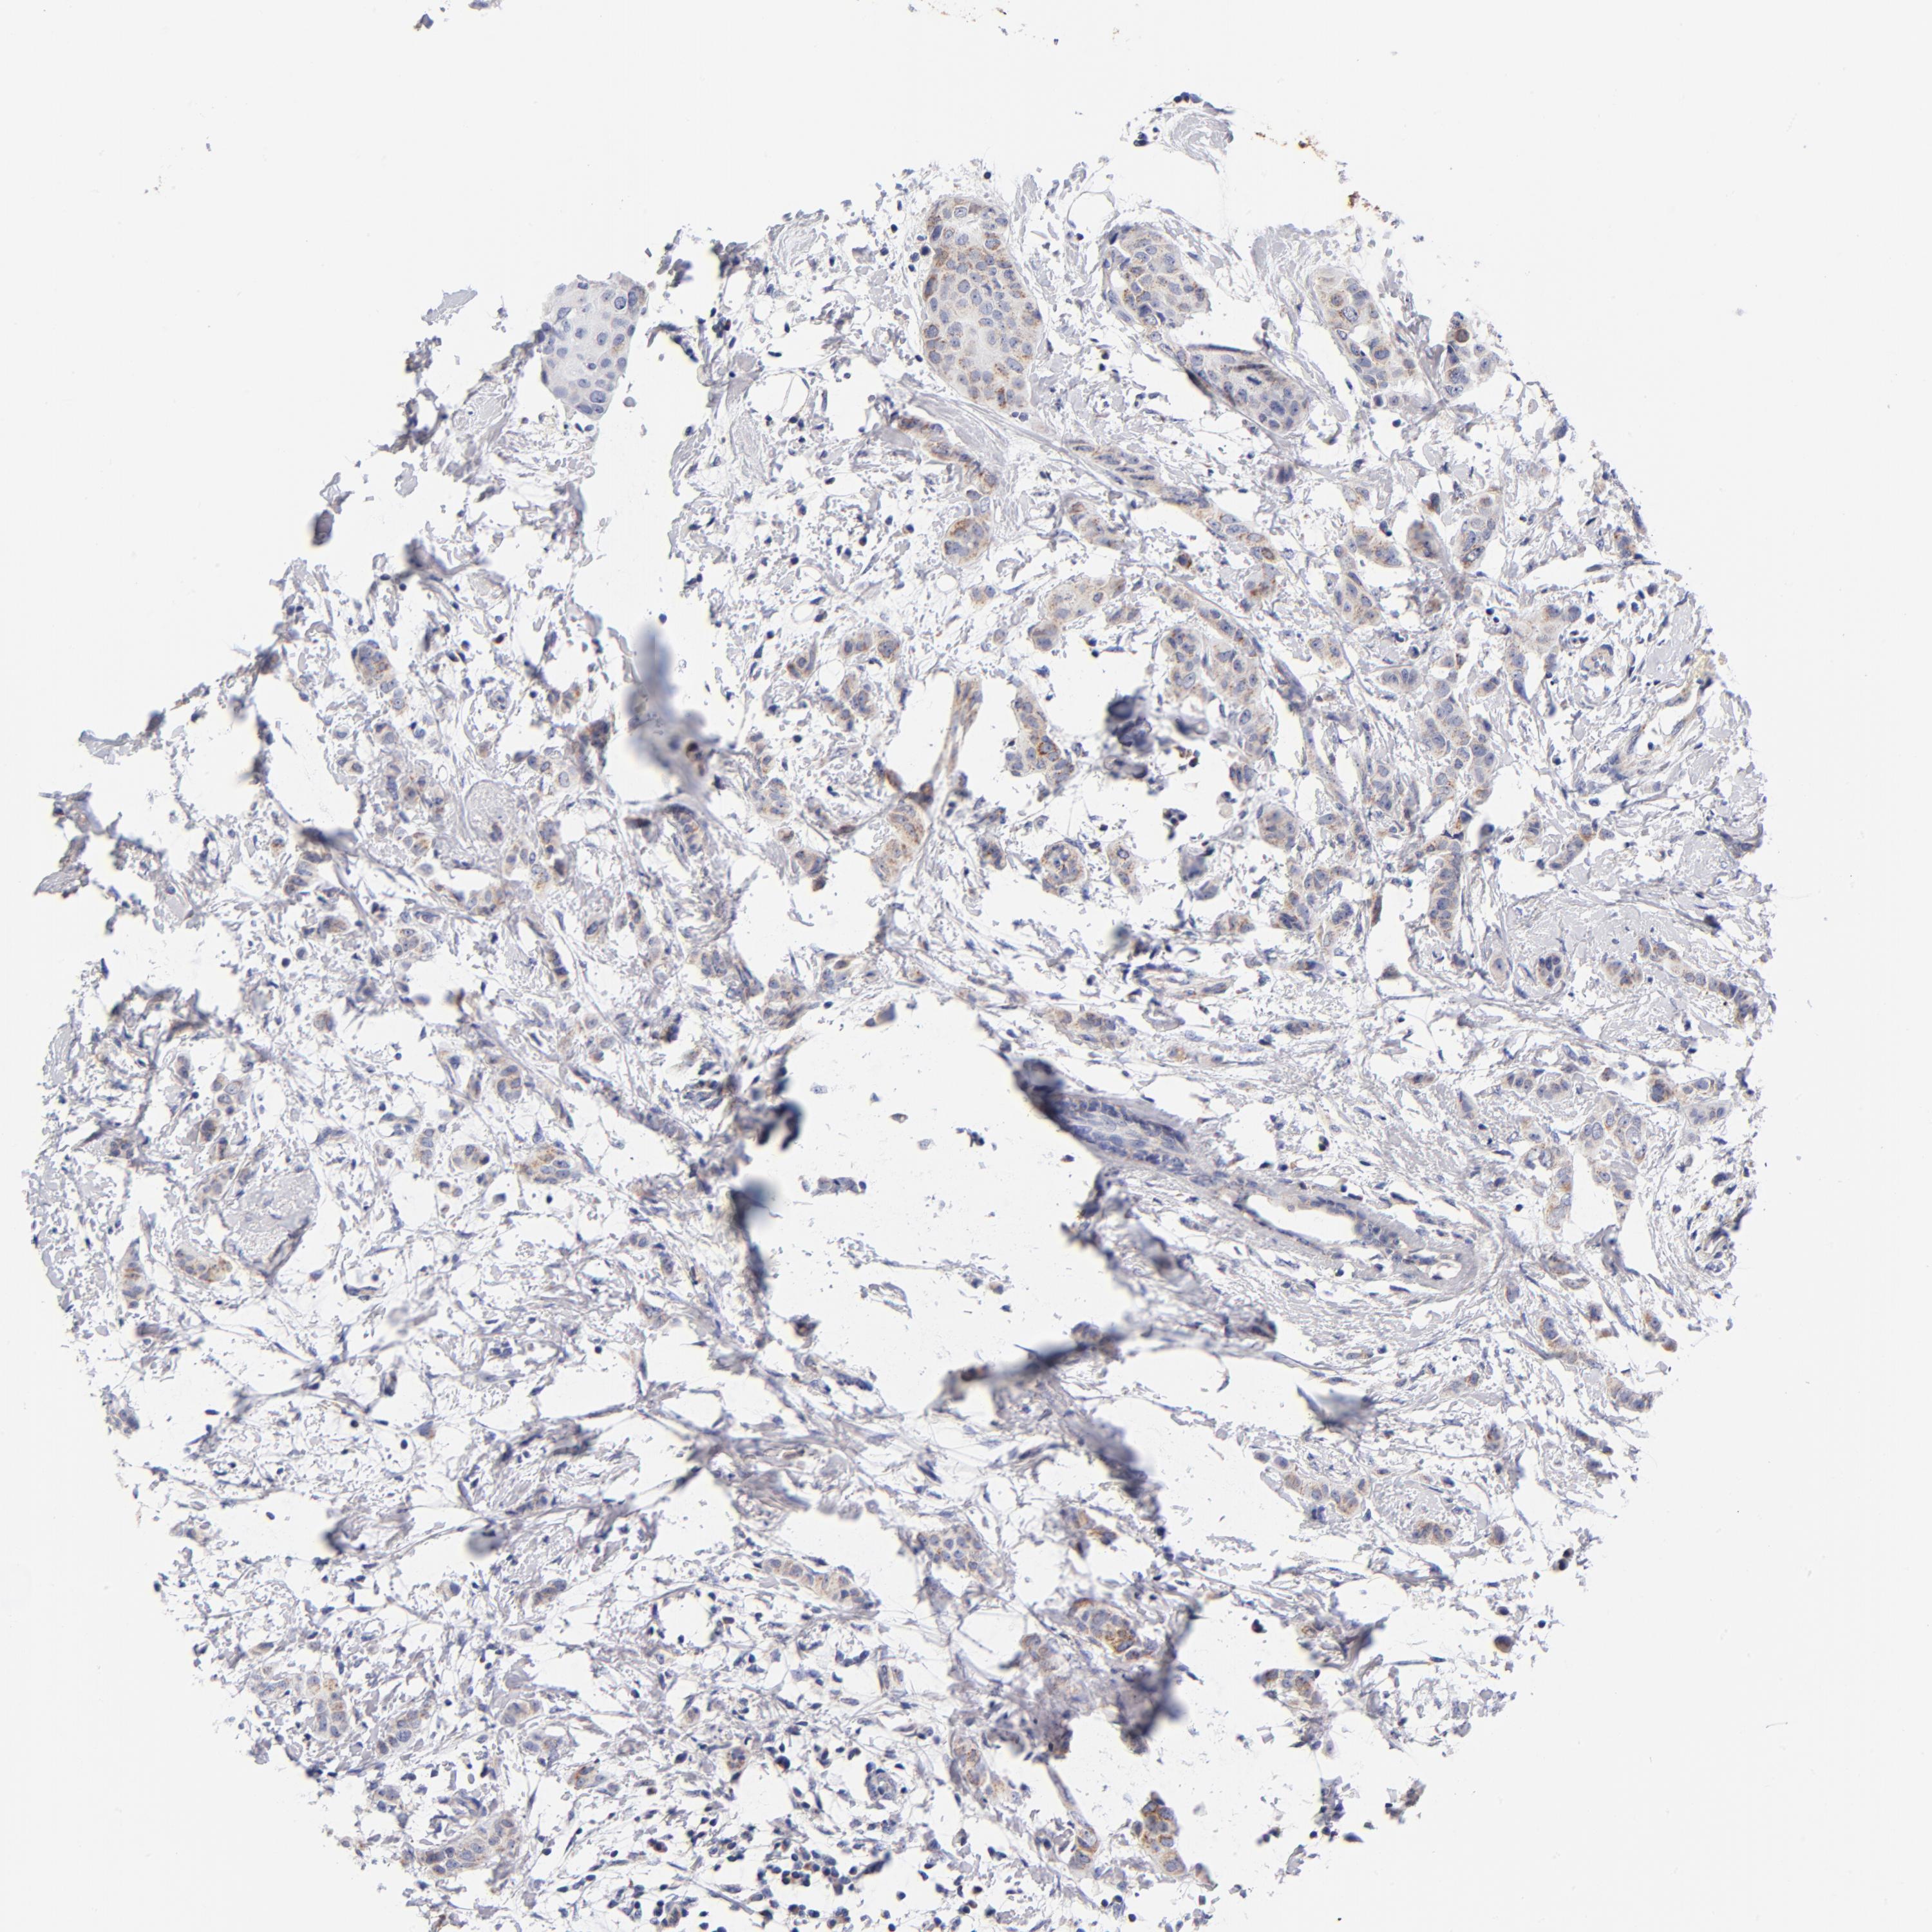

CANCER BREAST CANCER Show tissue menu

BRCA TCGA BRCA VALIDATION PROTEIN EXPRESSION

ANTIBODIES

AND

VALIDATION